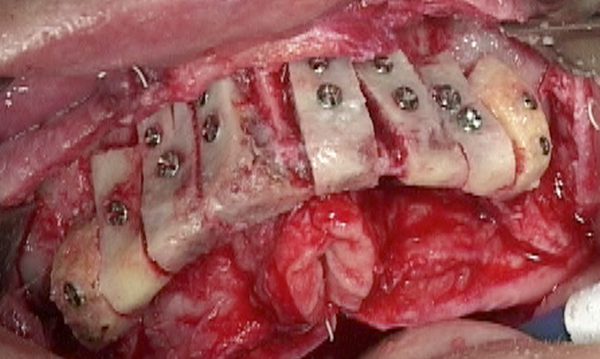

Immagine 6 Innesti ossei mascellari fissati con viti da osteosintesi (Osteomed, Allison, Texas, USA)